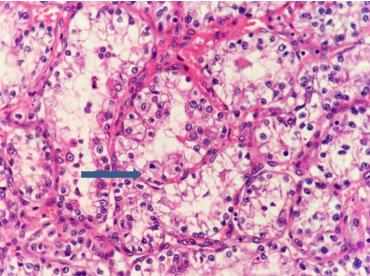

2例眼眶肿物切除标本镜下见大部分肿瘤细胞细胞质透亮,呈实性片巢状、腺管状、腺泡状排列(图4),核小,形状不一,部分核空泡状,可见核仁和核分裂象,例4可见肿瘤侵犯骨组织(图5)。肿瘤细胞质特殊染色PAS(+),不耐淀粉酶消化。免疫组织化学染色显示肿瘤细胞CK、VIM、CK8、EMA、CD10、PAX8阳性,CK7、CK19、CK20、S-100、SYN、CHG、HMB45、SMA、LCA、CD68均为阴性,增殖活性Ki-67指数为20%~30%。例4和例5结合形态、免疫组织化学及病史,符合转移性CC-RCC(表2)。

20230621103609_4710.png

图4 光镜下观察例5患者左眼眶转移性CC-RCC,部分区肿瘤细胞呈腺泡状排列,并见核分裂象(箭头;HE,×400)

Figure 4 Orbital metastatic CC-RCC (case 5) showed some tumor cells with alveolar architecture and mitotic figure (arrow; IHC, ×400)